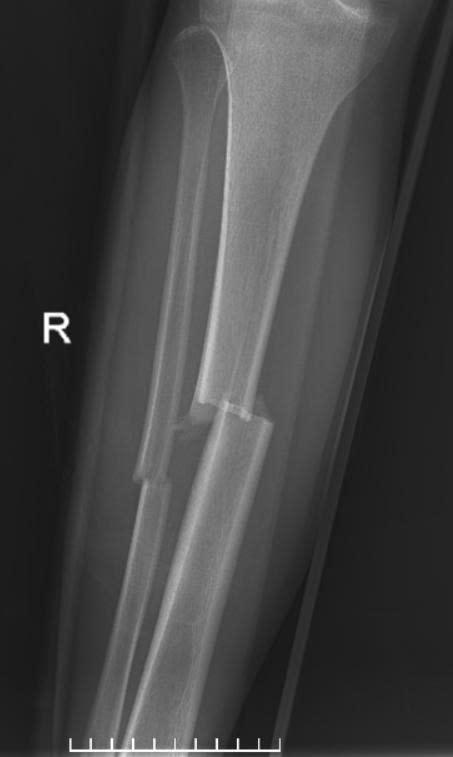

Sau hội chẩn chuyên môn, người bệnh được chỉ định phẫu thuật kết hợp xương dưới hướng dẫn của hệ thống màn hình tăng sáng (C-arm). Đây là thiết bị hiện đại hỗ trợ bác sĩ quan sát rõ vị trí ổ gãy trong suốt quá trình phẫu thuật, giúp nắn chỉnh xương về đúng trục giải phẫu và đặt dụng cụ cố định xương một cách chính xác, hạn chế tối đa sang chấn cho người bệnh.

Ca phẫu thuật được tiến hành ngay trong đêm và diễn ra thuận lợi. Các bác sĩ đã cố định vững chắc ổ gãy, xử trí tốt phần mềm và vết thương hở, tạo điều kiện thuận lợi cho quá trình liền xương và phục hồi chức năng vận động. Sau 6 ngày điều trị, tình trạng người bệnh ổn định và được xuất viện theo đúng dự kiến.